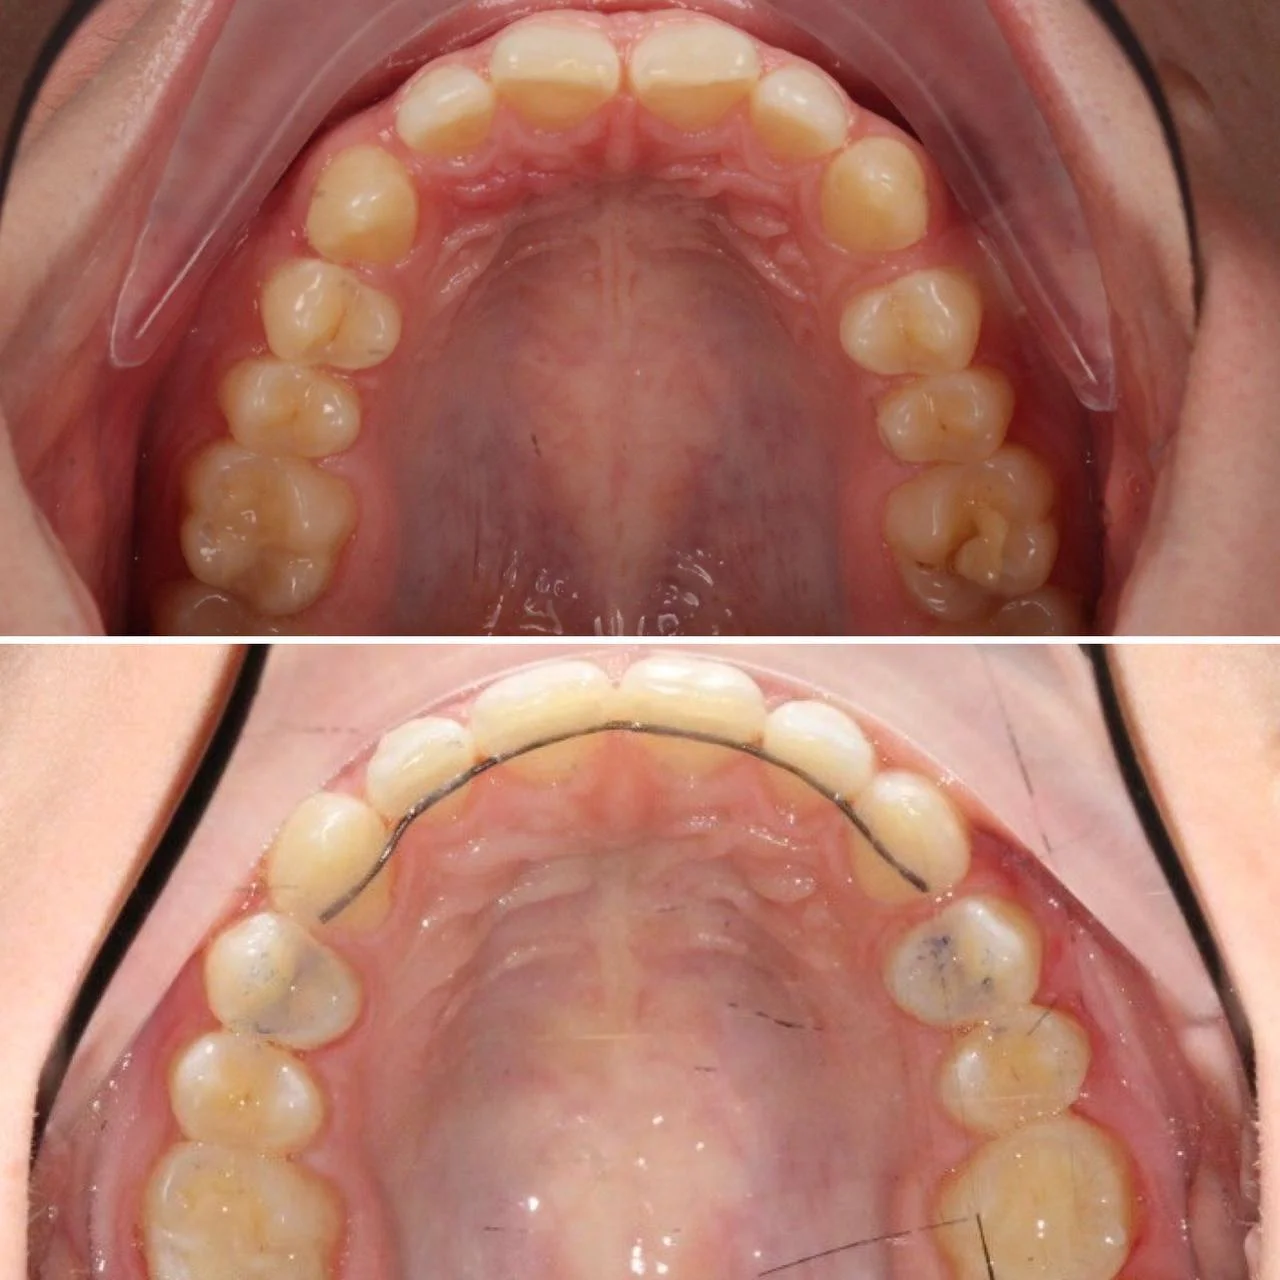

Скученность зубов, обе челюсти сужены — зубам не хватало места в ряду.

Брекет-система на обе челюсти. Расширить зубные дуги и убрать скученность. Срок — около 1,5 лет.

Проблема: Пациентка обратилась с одной жалобой — неровные зубы. При осмотре обнаружили, что обе челюсти сужены, зубам банально не хватает места, отсюда скученность. Зубы здоровые, ортопедия не нужна — чисто ортодонтический случай.

Решение: Установили брекеты на обе челюсти. Расширили дуги, убрали скученность — всё за 15 месяцев. Визиты раз в 4–6 недель для замены дуг. После снятия зафиксировали ретейнеры на обе челюсти, сняли сканы для кап. Ортопед подтвердил, что протезирование не требуется. Терапевт рекомендовал лечение — пациентка записана.